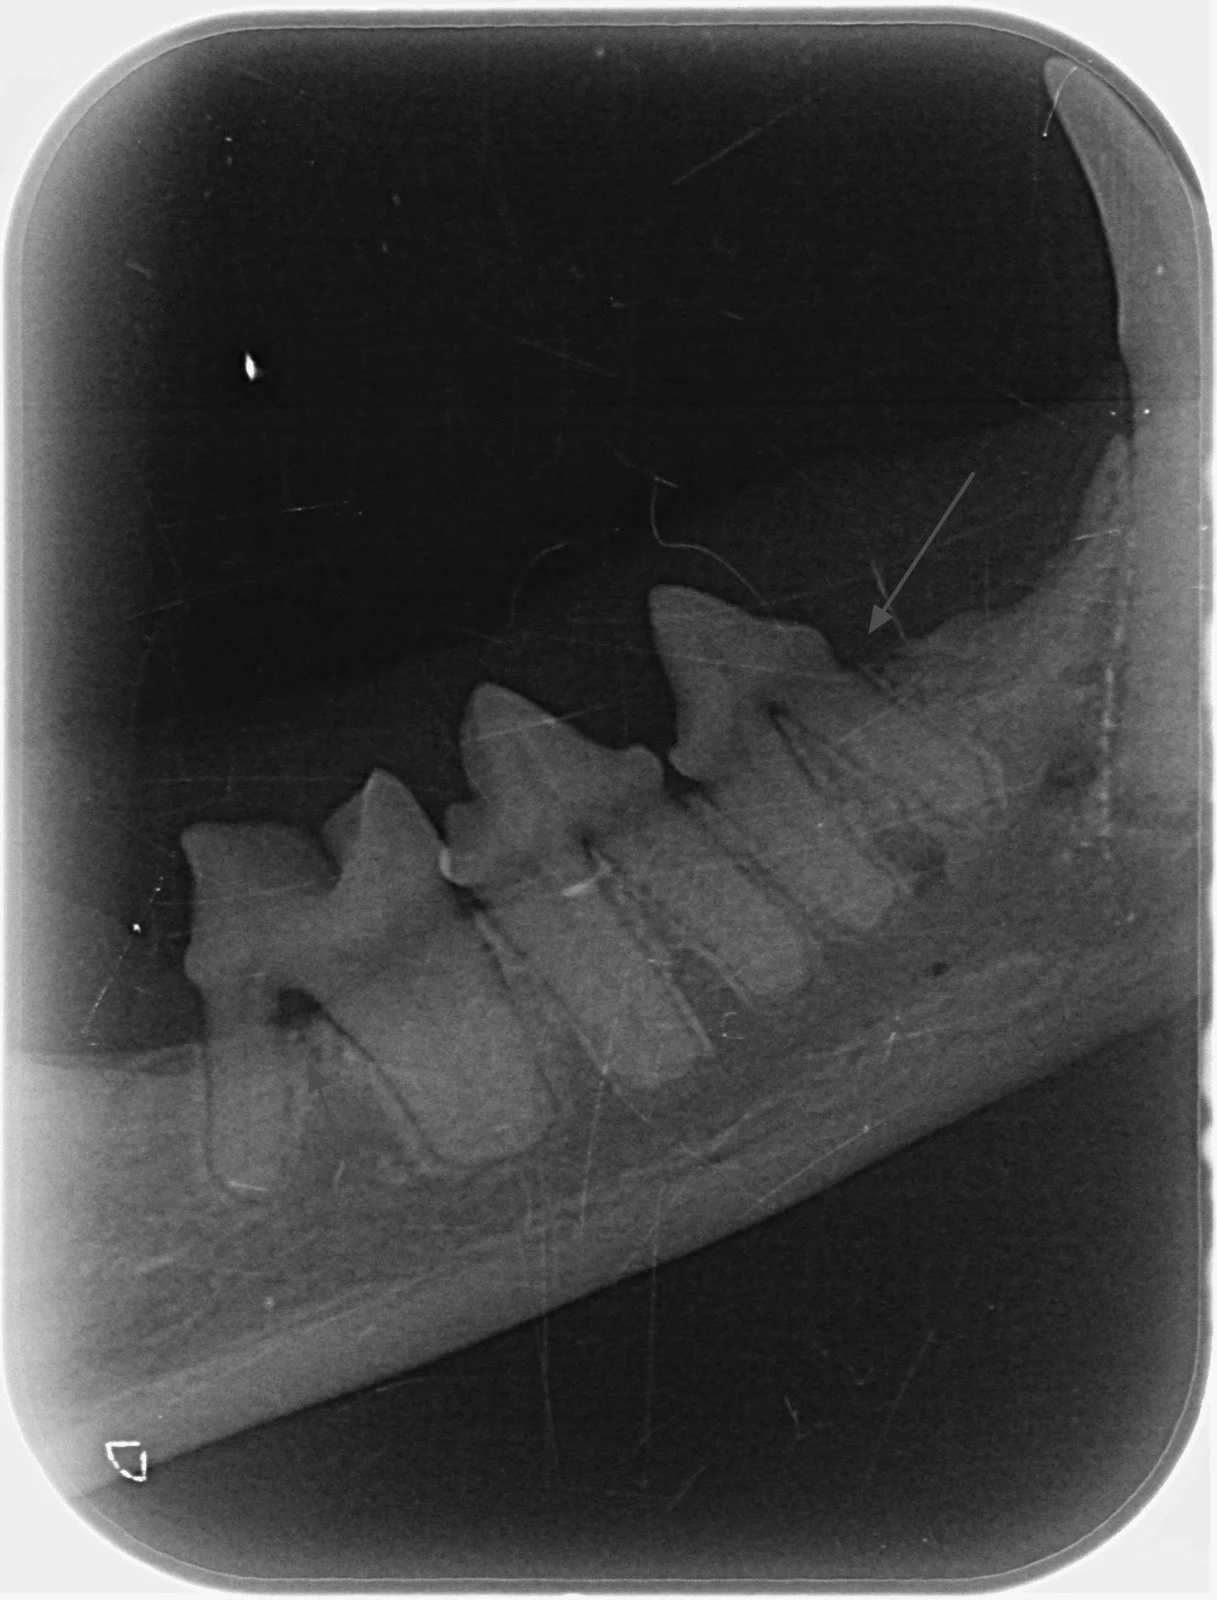

Problemele dentare sunt printre cele mai frecvente afecțiuni întâlnite la câini și pisici, însă multe dintre ele rămân ascunse sub gingie și nu pot fi observate la o simplă examinare vizuală. Radiografia intraorală veterinară este una dintre cele mai importante metode de diagnostic în stomatologia veterinară modernă, deoarece permite evaluarea detaliată a dinților, rădăcinilor și osului alveolar.